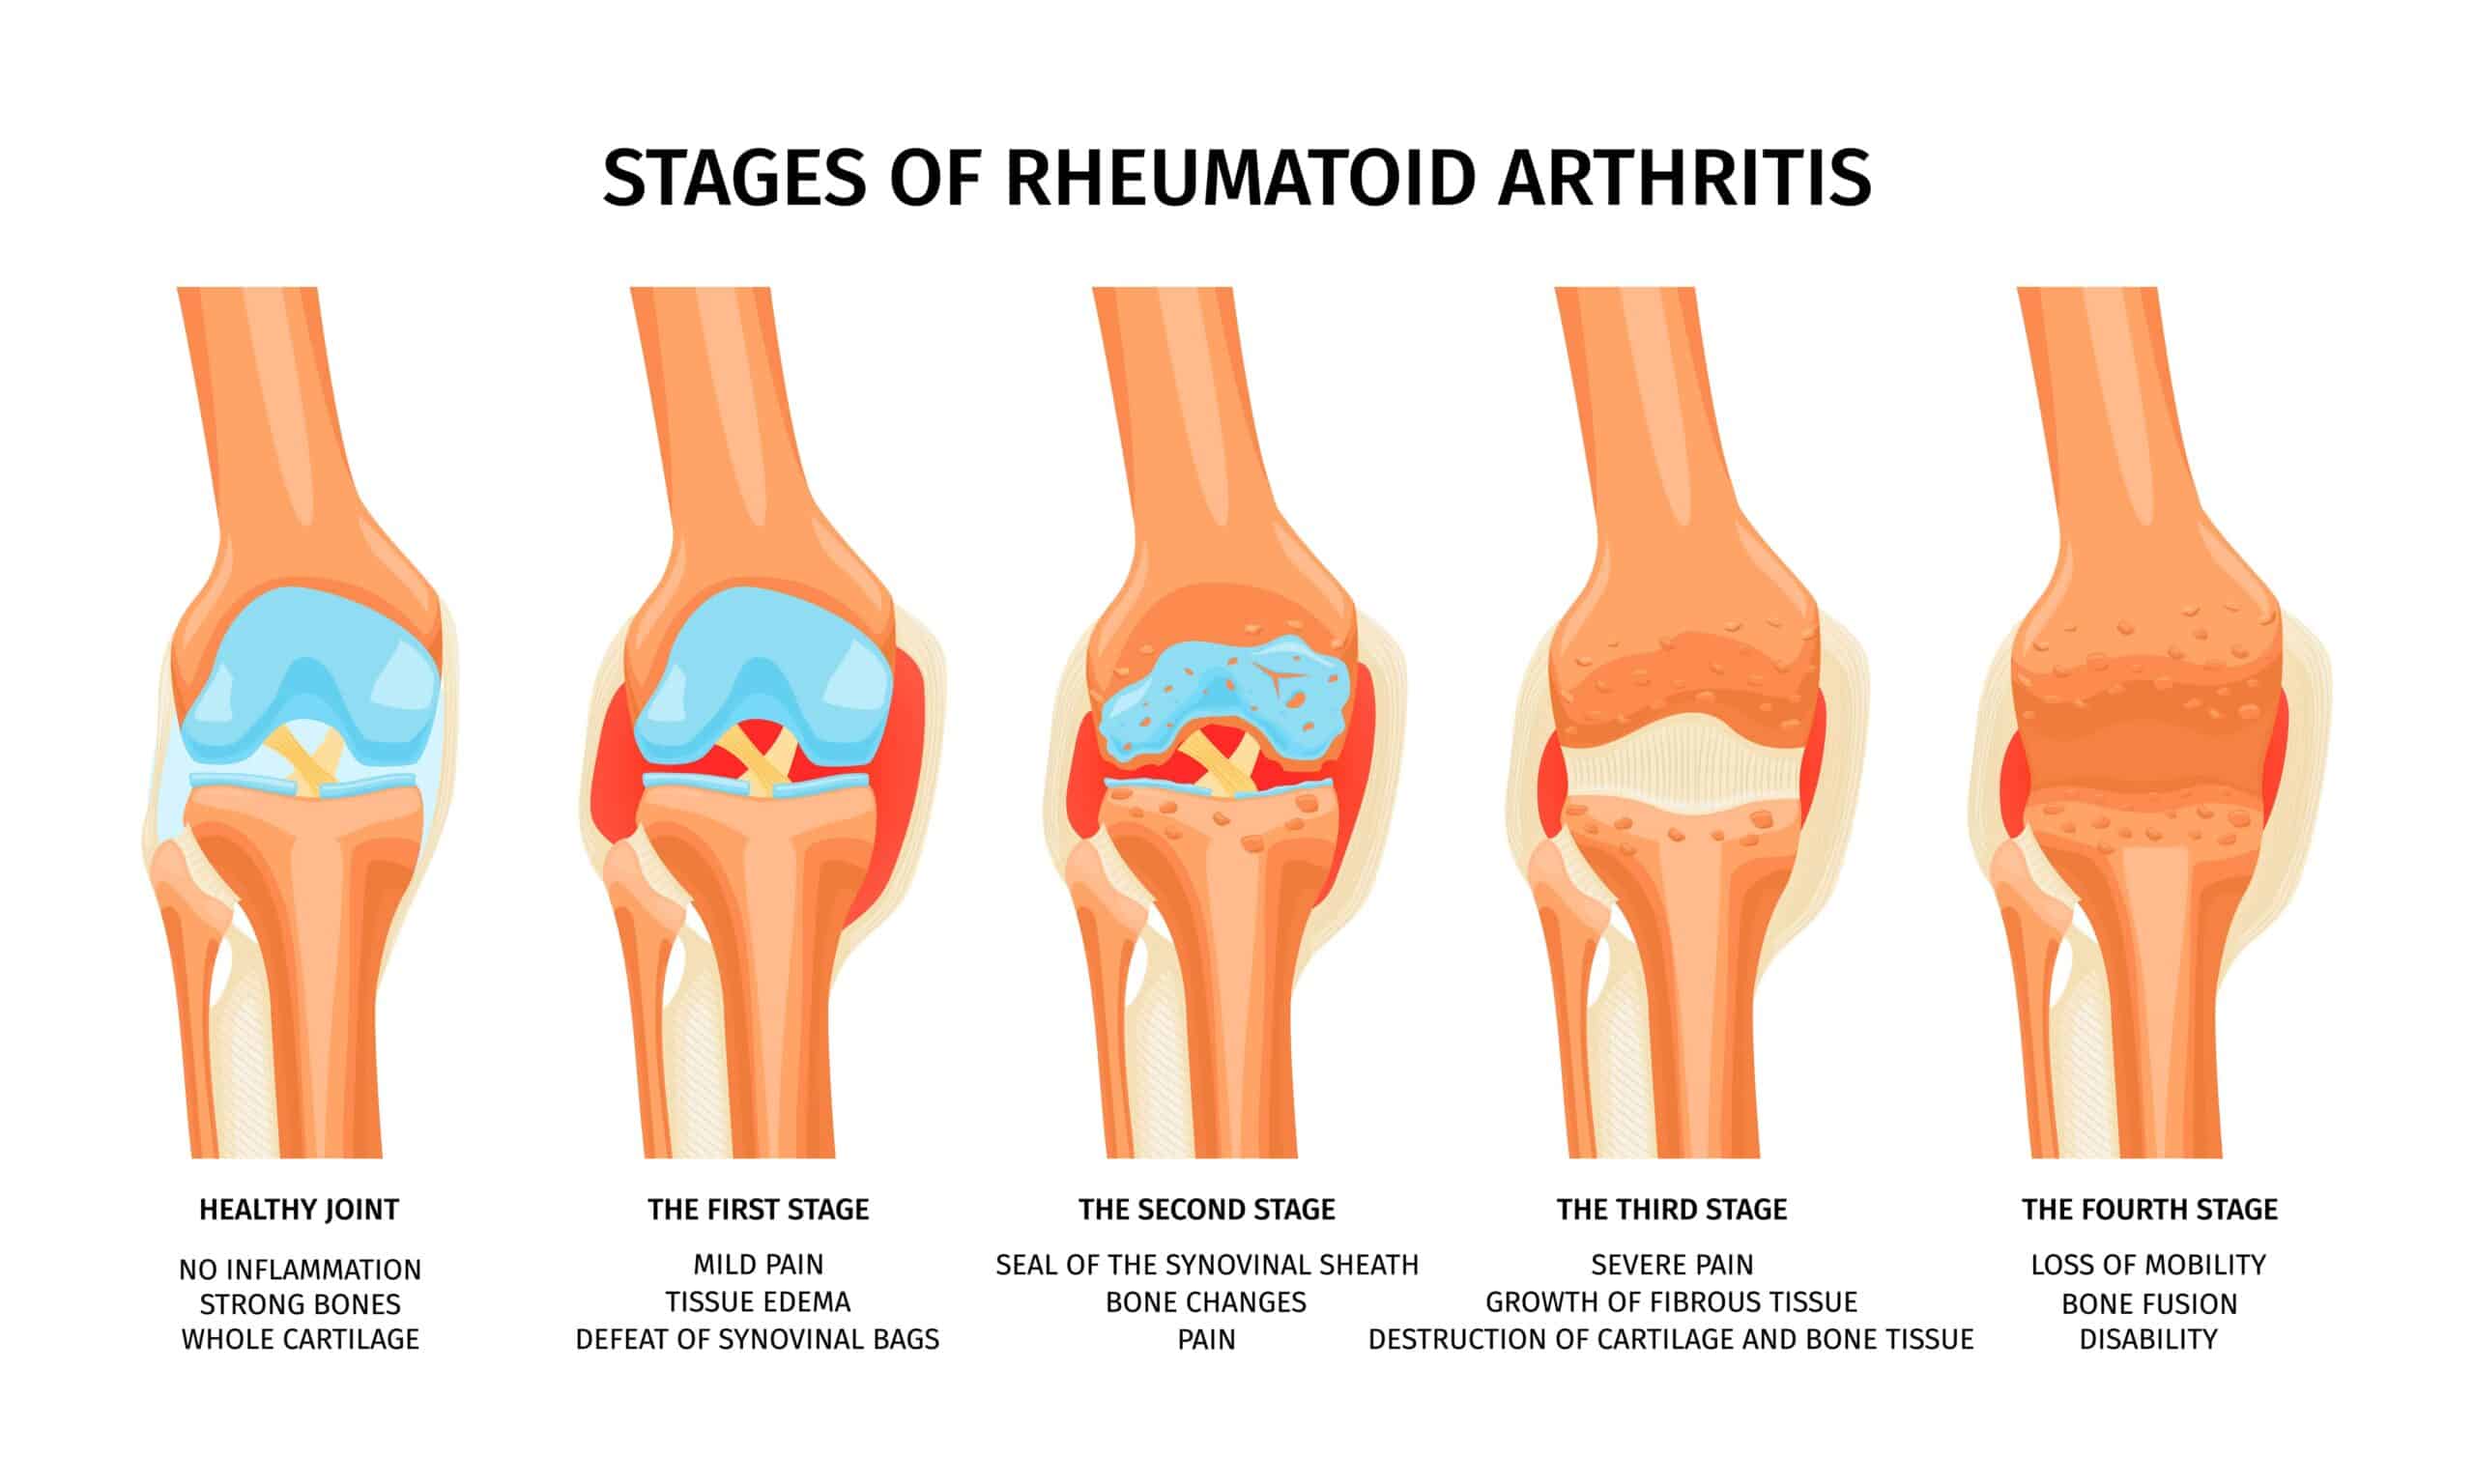

Артритът е изтощително състояние, което засяга милиони хора по света, причинявайки възпаление на ставите, болка и скованост. Традиционните методи на лечение са насочени към контролиране на симптомите и забавяне на прогресията на болестта. Но последните постижения в регенеративната медицина предоставят потенциален пробив в терапията на артрит: автоложни екзозоми. Тези малки везикули, извлечени от собствените клетки на пациента, имат огромен потенциал за облекчаване на симптомите на артрит и подобряване на качеството на живот на хората с това хронично състояние.

Автоложните екзозоми проявяват терапевтичните си ефекти чрез въздействие върху ключови аспекти на патогенезата на артрита. Тези малки везикули таргетират основните механизми, допринасящи за симптомите на артрит, водейки до комплексно облекчаване на болката и възпалението. Основните механизми включват намаляване на възпалението и имунния отговор, стимулиране на възстановяването и регенерацията на тъканите и модулиране на възприятието за болка.

Възпалението е ключов признак на артрита, причиняващо подуване на ставите и дискомфорт. Автоложните екзозоми притежават противовъзпалителни свойства, ефективно потискайки възпалителната каскада в ставите. Чрез взаимодействие с имунните клетки тези екзозоми регулират имунния отговор, намалявайки прекомерното възпаление и подпомагат по-балансирана имунна среда.

Освен това автоложните екзозоми играят важна роля в стимулирането на възстановяването и регенерацията на тъканите. Те съдържат биоактивни молекули, които стимулират производството на нови клетки и компоненти на извънклетъчната матрица, подпомагайки възстановяването на увредените ставни тъкани. Този регенеративен потенциал предлага големи перспективи за хората с артрит, като таргетира причината за състоянието и осигурява дългосрочно облекчение и подобрена функция на ставите.